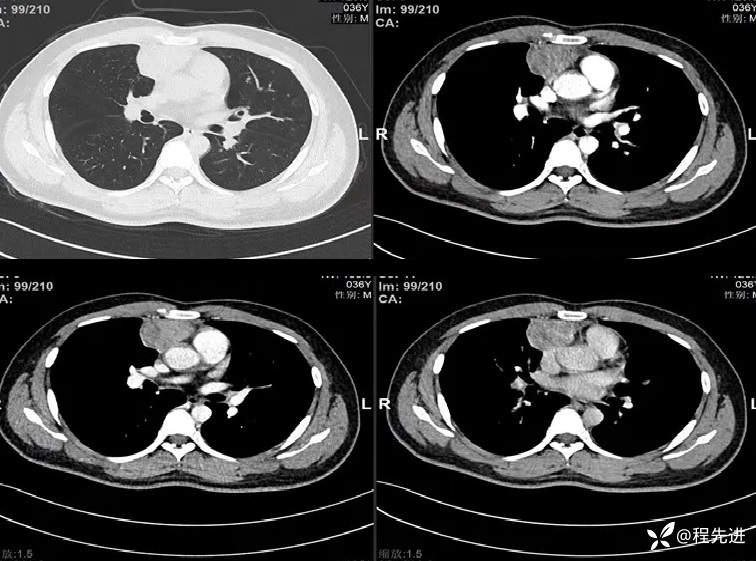

患者性别:男

患者年龄:36岁

主诉:胸痛1个月

现病史:患者1月前偶有胸痛,行胸部CT检查提示前纵隔占位性病变。病来饮食睡眠可,二便正常,体重无明显变化。